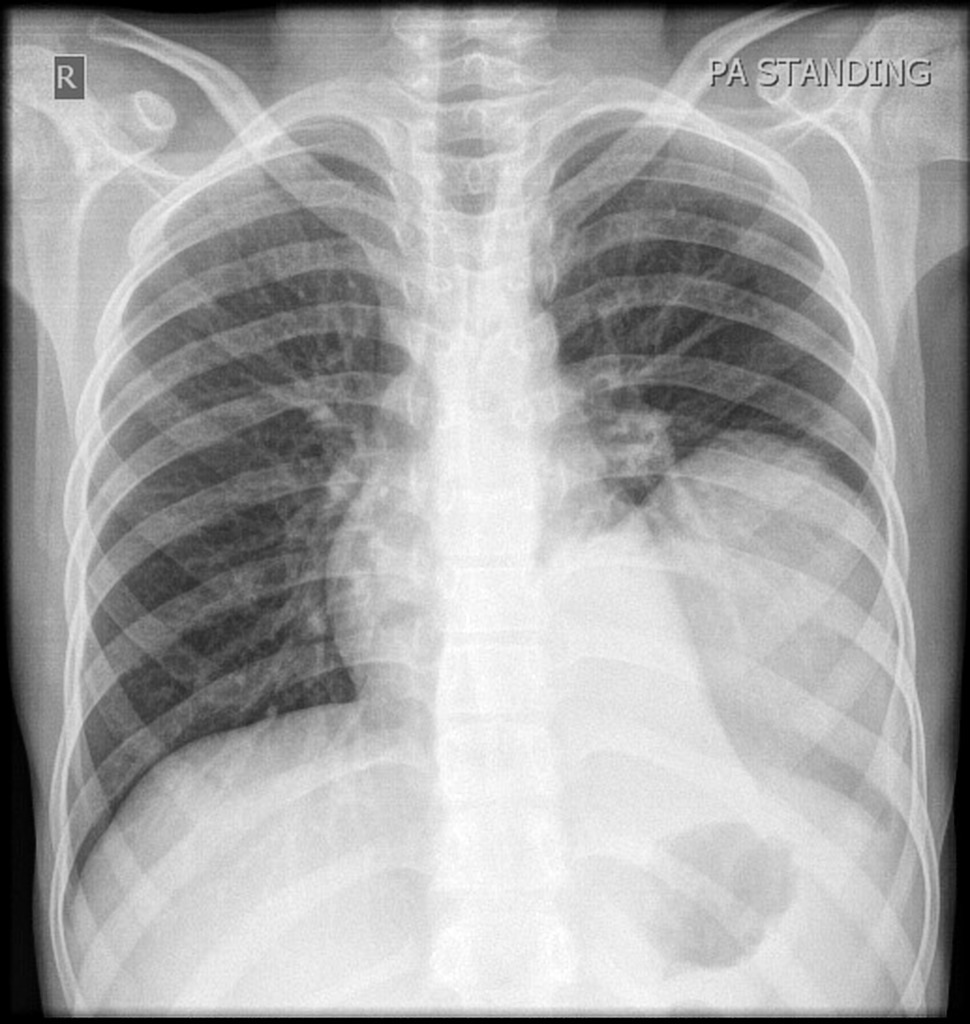

PACIENTE 35 ANOS, SEXO MASCULINO, DISPNÉIA HÁ 4 DIAS.

opacidades em vidro fosco difusas associadas a espessamento de septos interlobulares (crazy paving)

PROTEINOSE ALVEOLAR